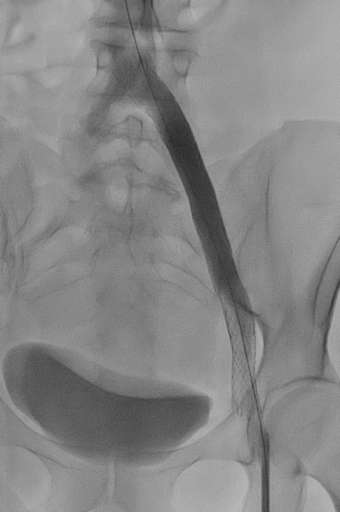

תמונות מהצנתור:

בתמונה 1:

- ונוגרפיה – היצרות של וריד כסל חיצוני ומשותף משמאל, התפתחות מעקפים מורחבים המנקזים באופן איטי את הגף התחתון.

- וריד צר- תכלת

- וריד עוקף מורחב- צהוב

- אזור ההיצרות הקשה – סגול

בתמונה 2:

- ורידים מורחבים "גודש ורידי אגן"